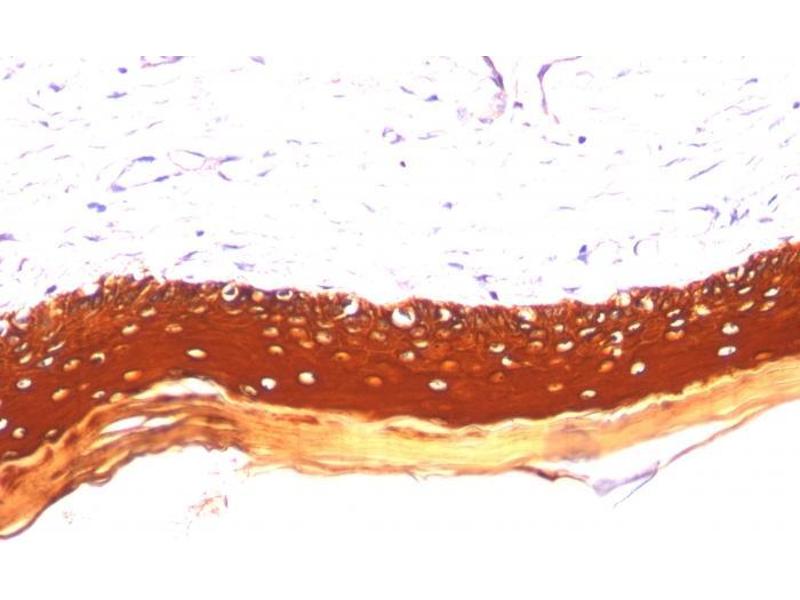

The 小鼠 单克隆 anti-Keratin 77 antibody is suitable to detect Keratin 77 in samples from 人 和 大鼠. It has been validated for IHC 和 StM.

Immunohistochemistry (IHC), Staining Methods (StM)

This MAb recognizes the 56.5 kDa (CK10), 50 kDa (CK14), 50 kDa (CK15), 48 kDa (CK16), 40 kDa (CK19) keratins of the acidic (Type I or LMW) subfamily. Twenty human keratins are resolved with two-dimensional gel electrophoresis into acidic (pI 6.0) subfamilies. The acidic keratins have molecular weights (MW) of 56.5, 55, 51, 50, 50', 48, 46, 45, and 40 kDa. Many studies have shown the usefulness of keratins as markers in cancer research and tumor diagnosis.

Positive Control: Skin, Squamous cell carcinoma (SCC).

Known Application: Immunohistochemistry (Formalin-fixed) (0.1-0.2 μg/mL for 30 min at RT)(Staining of formalin-fixed tissues requires boiling tissue sections in 10 mM citrate buffer, pH 6.0, for 10-20 min followed by cooling at RT for 20 minutes)Optimal dilution for a specific application should be determined.